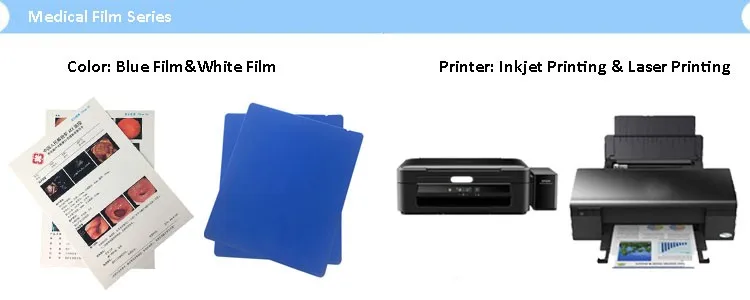

Лазерная камера для печати медицинских изображений на пленке стандарт dicom